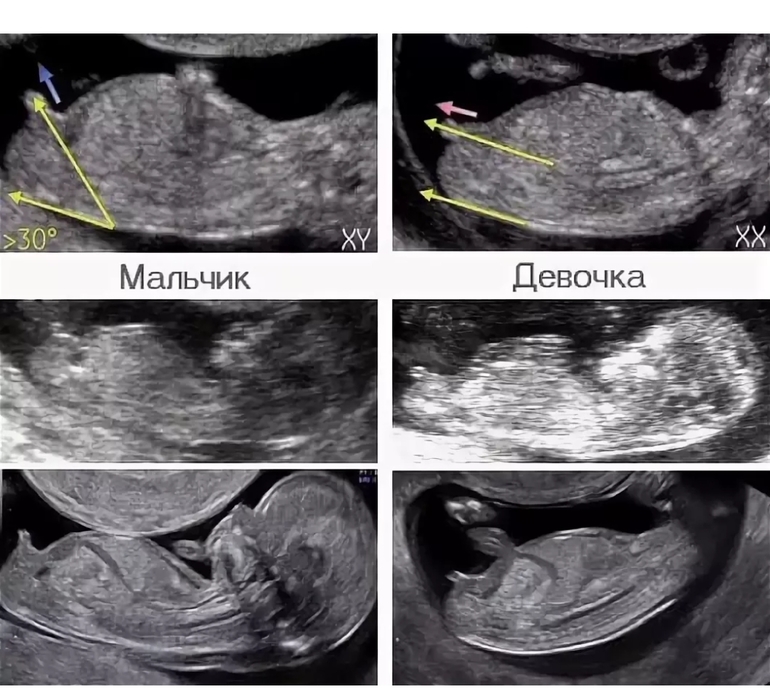

И наше фото! 😍

Не поленилась я и нашла в интернете, как определить пол на таком сроке! 😅Как думаете к какому варианту ближе мы? 😁